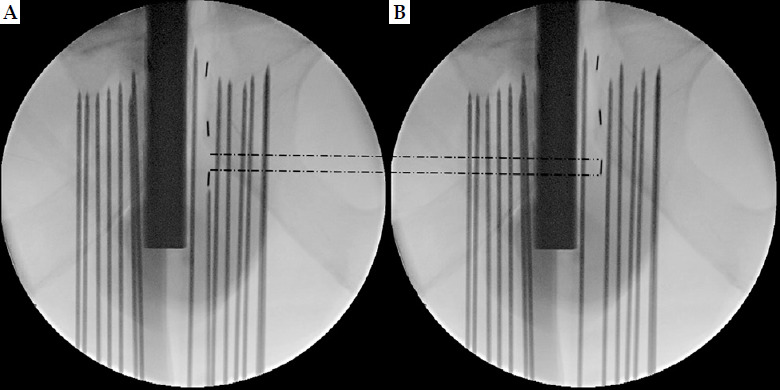

Purpose: Displacement minimization of seeds is crucial during surgery in brachytherapy; however, only a few reports have compared the operability of different seeds. TheraStrand-SL is a seed, in which TheraAGX100 is wrapped in polyglactin 910 thread, and intra-prostatic displacement is expected to be reduced compared with that of Thera-AGX100, owing to the complex shape of TheraStrand-SL. We conducted a prospective study on the operability and treatment outcomes of TheraAGX100 and TheraStrand-SL placement by a single operator.

Material and methods: The study included 69 patients who received brachytherapy for prostate cancer. Endpoints were comparisons of intra- and post-treatment dose-volume histograms, seed displacement incidence rate, seed displacement distance, seed migration/dropout incidence rate, and adverse events incidence rate between TheraAGX100 (n = 25) and TheraStrand-SL (n = 44) groups.

Results: The intra-prostatic displacement incidence rate was significantly lower in the TheraStrand-SL group than in the TheraAGX100 group (TheraAGX100 group: 96.0%; TheraStrand-SL group: 11.4%). Further, the intra-prostatic displacement count per case tended to be lower in the TheraStrand-SL group than in the TheraAGX100 group. Additionally, a comparison of displacement distance per case showed that the TheraStrand-SL group (2.01 mm) had a statistically significantly shorter distance than the TheraAGX100 group (9.22 mm). No significant differences between the two groups were observed in terms of migration, explanted dropout seed count, dose-volume histograms, and adverse events incidence rate.

Conclusions: Our study demonstrated the usefulness of TheraStrand-SL against intra-prostatic displacement. We expect TheraStrand-SL to have further applications in brachytherapy, including focal therapy.